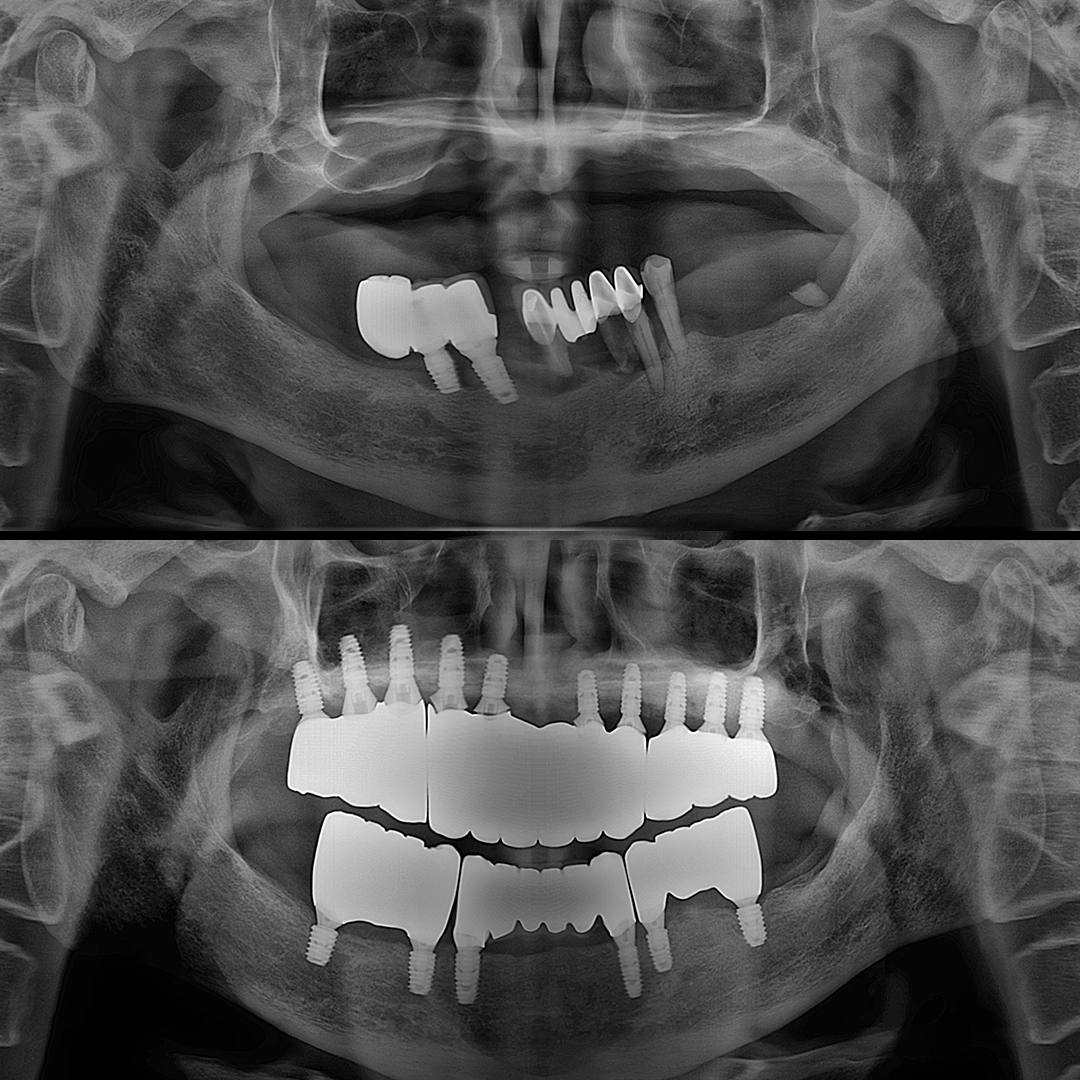

전체 임플란트

상·하악 전체 치아를 대체하는 임플란트로 최소한의 식립을 통해

자연치아와 비슷한 기능을 수행할 수 있도록 합니다.